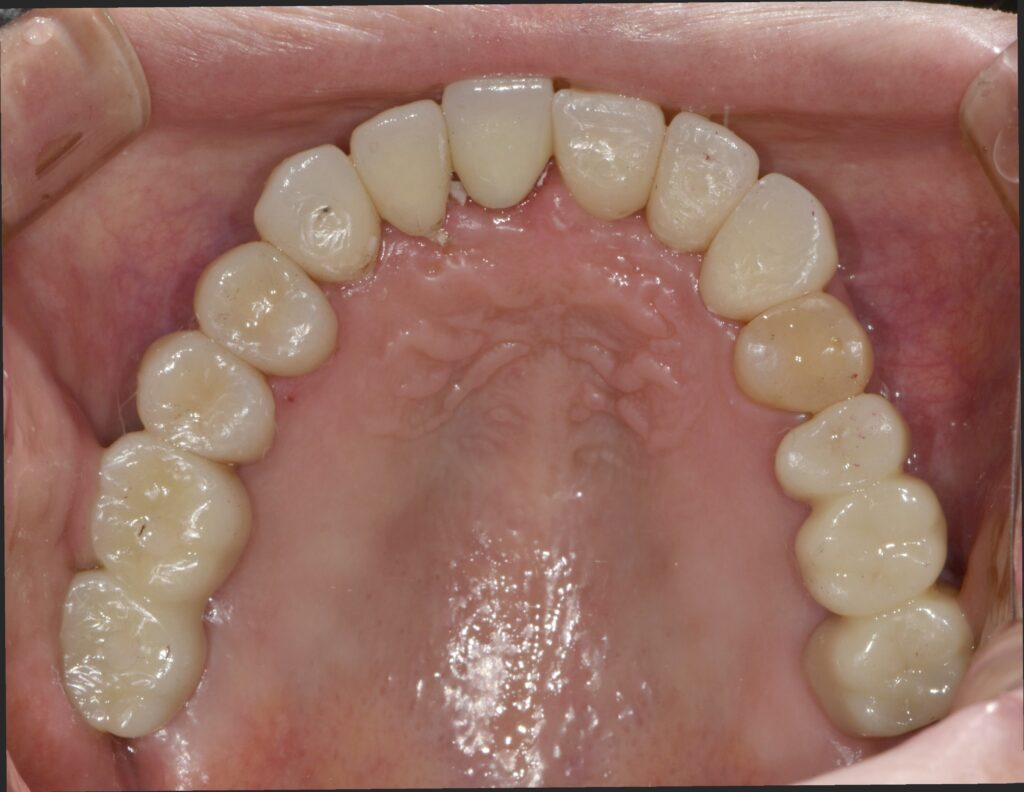

임플란트 식립 후 3개월 뒤에 임플란트와 뼈가 단단하게 붙은 것을 확인한 뒤 본을 떠서 임시치아를 만들었습니다.

1개월 동안 임시치아를 사용하면서 교합(치아가 물리는 관계)을 확인하고 모든 것이 편안해졌을 때 한 번 더 본을 떠서 최종 보철로 이행했습니다.

이렇게 임시치아 기간을 거쳐서 최종 보철을 완성하는 과정은 치료가 빨리 끝나길 바라는 환자분들도 힘드시겠지만 사실 저희 의료진도 힘들기는 마찬가지입니다.

하지만 임시 보철 기간은 반드시 가져야 합니다.

어금니가 없는 채로 3개월 이상 지내셨기에 턱관절이 새로운 치아에 적응하는 시간이 필요하며

또 지내시면서 음식물이 끼진 않는지 음식물이 잘 씹히는지 치아가 걸리지는 않는지 등 많은 부분에 대해서 미리 살펴보고 개선해야 할 점은 미리 개선하여

최종 보철물을 만드는 것이 가장 좋은 결과를 낼 수 있기 때문이죠.

위와 같이 치료가 완료되었습니다. 상당히 깔끔하게 잘 치료되었네요. 총 치료 기간은 4개월 소요되었습니다.